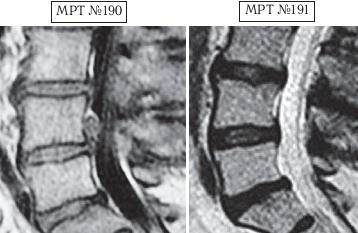

После операции стало легче, но боли полностью не прошли и онемение в ноге частично осталось. Не обращая на это внимания, парень продолжал упорно тренироваться, пытаясь одновременно «убить двух зайцев»: восстановиться после операции и подготовиться к очередным, но очень важным (для него на тот момент) соревнованиям. Однако здоровье подвело в самый неподходящий момент, соревнования он провалил. Дальше хуже — личные показатели упали, боли усилились. Опять обратился в нейрохирургию, где диагностировали секвестрированную грыжу в сегменте LIV-LV (МРТ № 190) и врачи снова предложили ему операцию. Ко всем прочим бедам от него отказался ещё и тренер, решив «не тратить попусту время» на такого спортсмена.

На МРТ № 190 наблюдается состояние поясничного отдела позвоночника после хирургического вмешательства в сегменте LV-SI, протрузии межпозвонковых дисков в сегментах LIII—LIV и LV-SI, грыжа межпозвонкового диска, осложнённая секвестром с краниальной миграцией в сегменте LIV—LV, стеноз спинномозгового канала.

На МРТ № 191 наблюдается состояние поясничного отдела позвоночника после лечения методом вертеброревитологии: отсутствие секвестрированной грыжи межпозвонкового диска, отсутствие стеноза спинномозгового канала.

Должен отметить, что это был на редкость дисциплинированный пациент, он строго выполнял все предписания и назначения. И, конечно же, результат не заставил себя ждать — между МРТ № 190 и МРТ № 191 разница всего три месяца! А буквально через полтора года он взошёл на пьедестал почёта. Это была настоящая его победа, в первую очередь над обстоятельствами, своими болезнями, недоверием окружающих и главное — над самим собой!